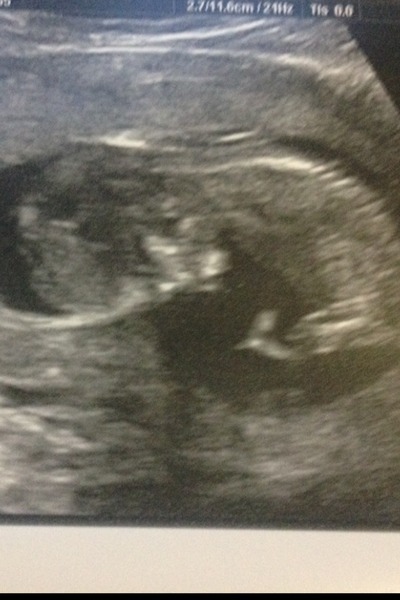

Finally got our scan, due date has changed from 21/06 to 24/06. NT measurement all seemed ok, mid risk at the moment but need to wait for blood to come back.

Baby was chilled out but then started kicking their legs once sonographer poked my tummy a bit. No chance of seeing the nub.